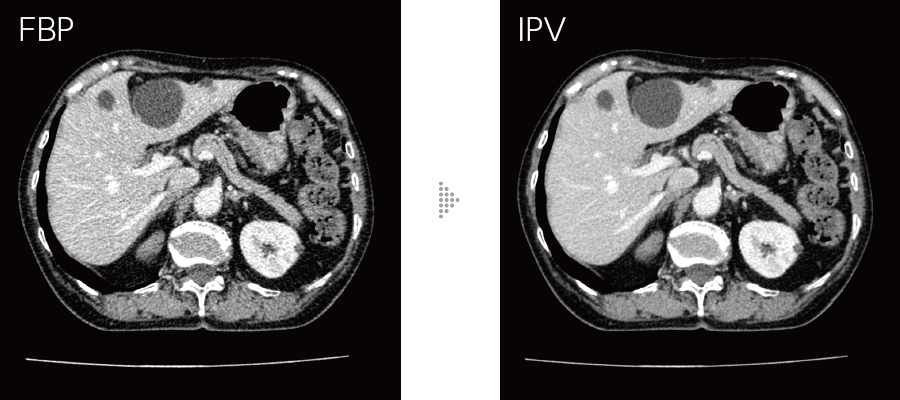

Our iterative reconstruction method, Intelli IPV, provides images that maintain their natural texture even at high noise reduction rates and their excellent visibility even at low doses, and does not require a dedicated operating room or additional hardware.

While adjusting the texture at a uniform ratio from high frequency to low frequency, the physical properties that affect visibility are made as close as FBP.

- *4 Compared to FBP. It was measured using Intelli IPV intensity level Strong5 and tested to a water phantom. Depending on the clinical task, patient size, anatomic location, and clinical examination, the effect obtained may be smaller.